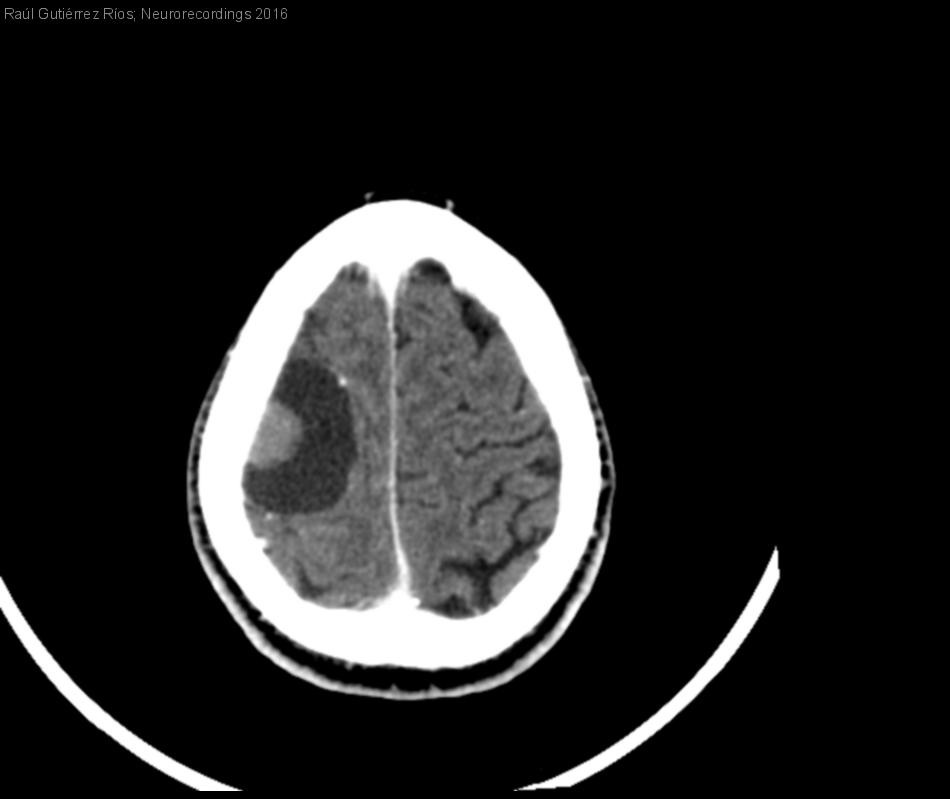

Meningioma quístico

Hombre | 67 años

Diagnóstico final: Meningioma microquístico. Quiste triquilemal